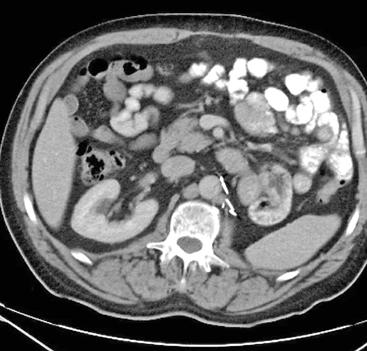

» Imagen médica de un riñón con cáncer.